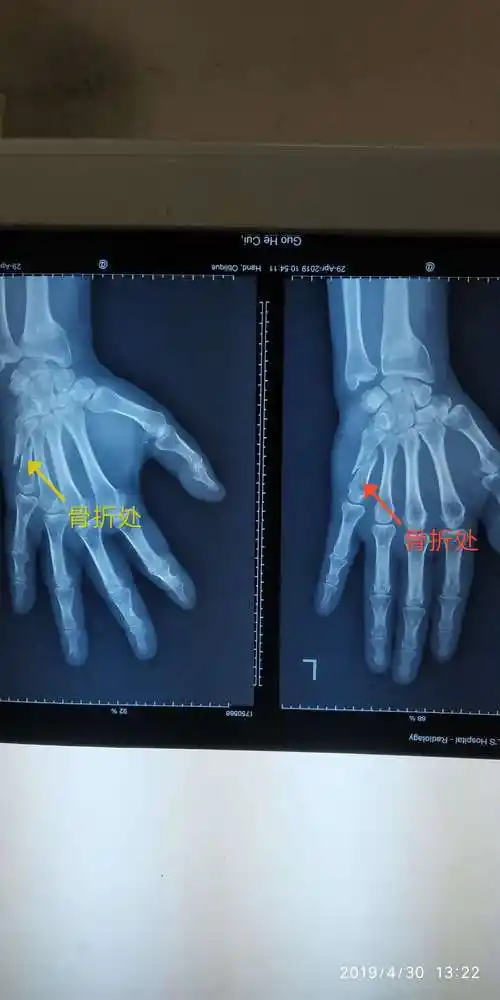

来医院急诊就诊,行x线片提示有右手中指第1节指骨近端骨折,涉及到关节

急诊拍摄断掌x线片示骨折情况.